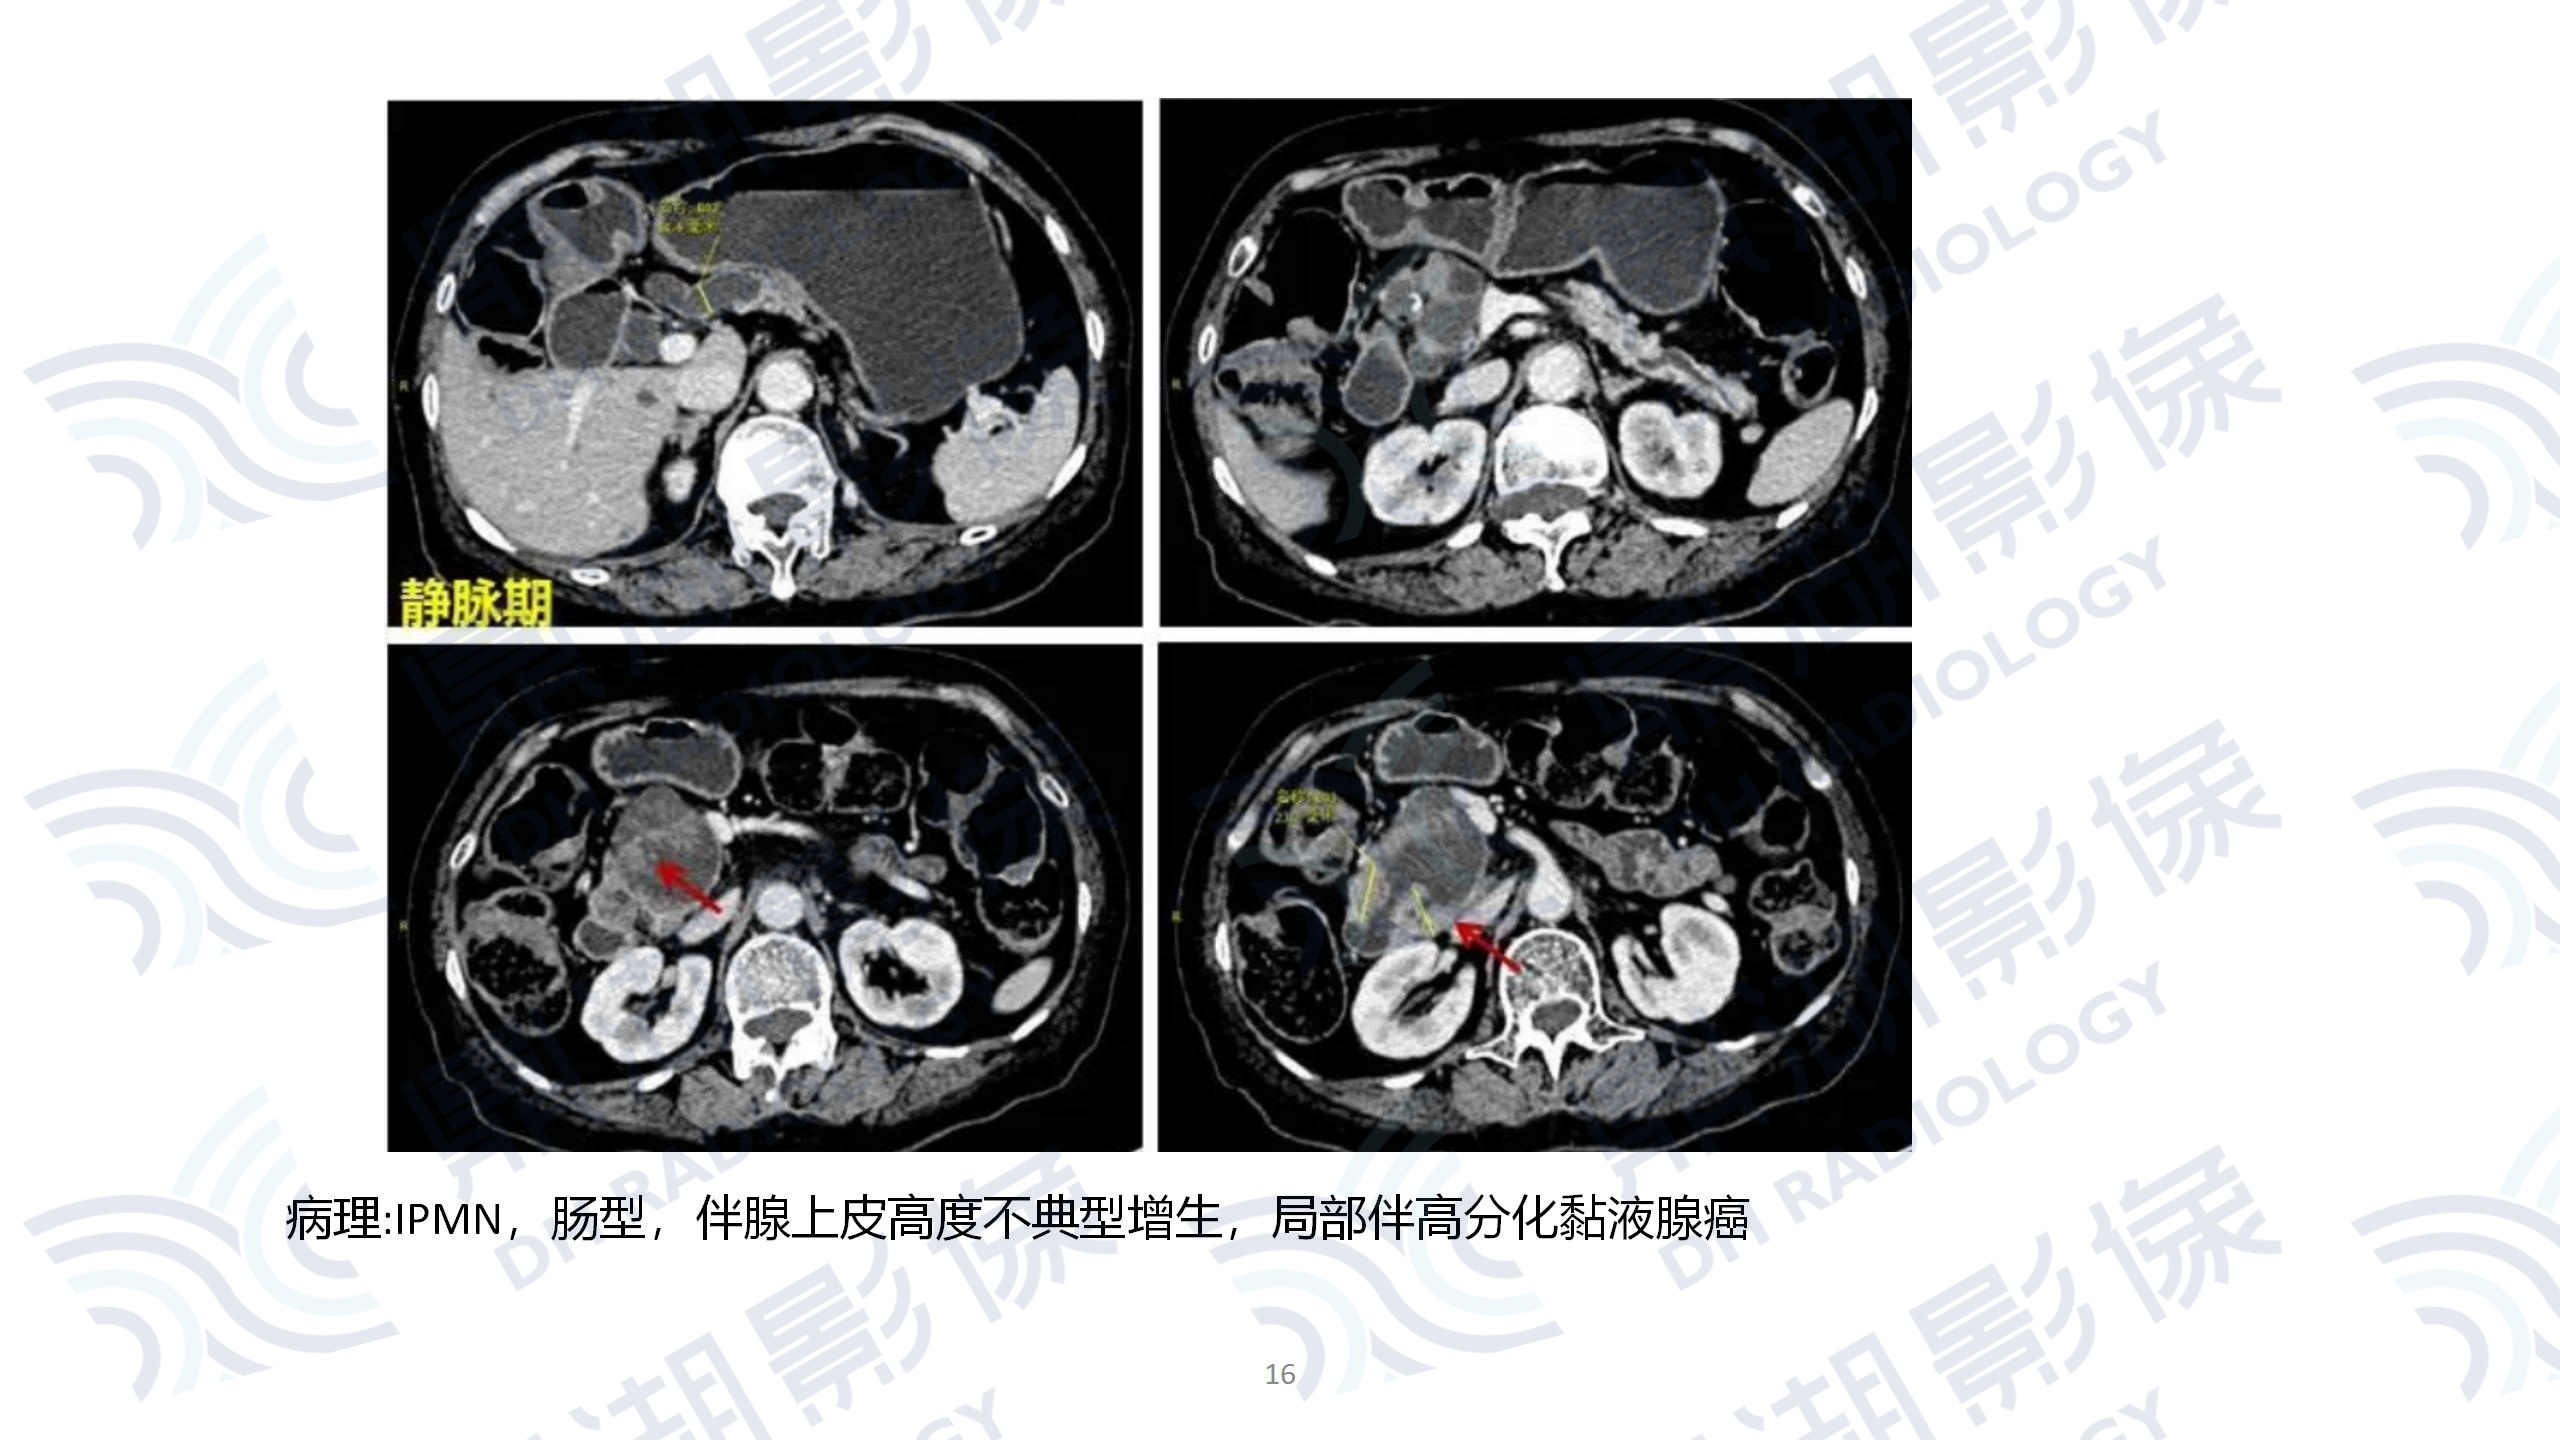

faf9bd7b569758137be2459a6d6358b2.jpg9dbb6dc40be4e83ac036465a293f7634.jpg64786b98144fd29747a02b3c3b25bf67.jpgbbeb9aad8dc251099799af04a61be571.jpg08bd065345df7d0d2b815b99938da241.jpgbd41e9d6233a178ffc615b3a9c18a2f1.jpg67d25d5fd4db7eaa226124eebb3d85e7.jpg2a6876b7d6716e60096536ed922ee8c1.jpg7f0255a99e57f71ee90d63f3df65a26f.jpga40f705b574187773a735d37963e700d.jpg0504c1d47a6ecf64a639652de1d7d87b.jpg66796921e3f062ccb333cff0d2d42926.jpg432be830c0c324773aa666d8c6db8df8.jpg3c3eade5ea39e2ebadca310ea8997056.jpg62971f2ae19dbdc6dbe418f7e93f9a66.jpg67a75fed3a589f8d51c41e3a432d1c3d.jpga3a7630d74a06bcd1367b7869c38e060.jpg85511e6307a90b305824ecc86c613c12.jpgde52548a6e0b62976f8c3c86d8608bfc.jpgf2cc8fe6db9171fef61134829e945a08.jpgfe97245386241567d65816ff04ec73a7.jpg945dad25a006f173fe10e443f4b41aaf.jpgdd8f01f0ad2cb7e9668e69d990962078.jpg